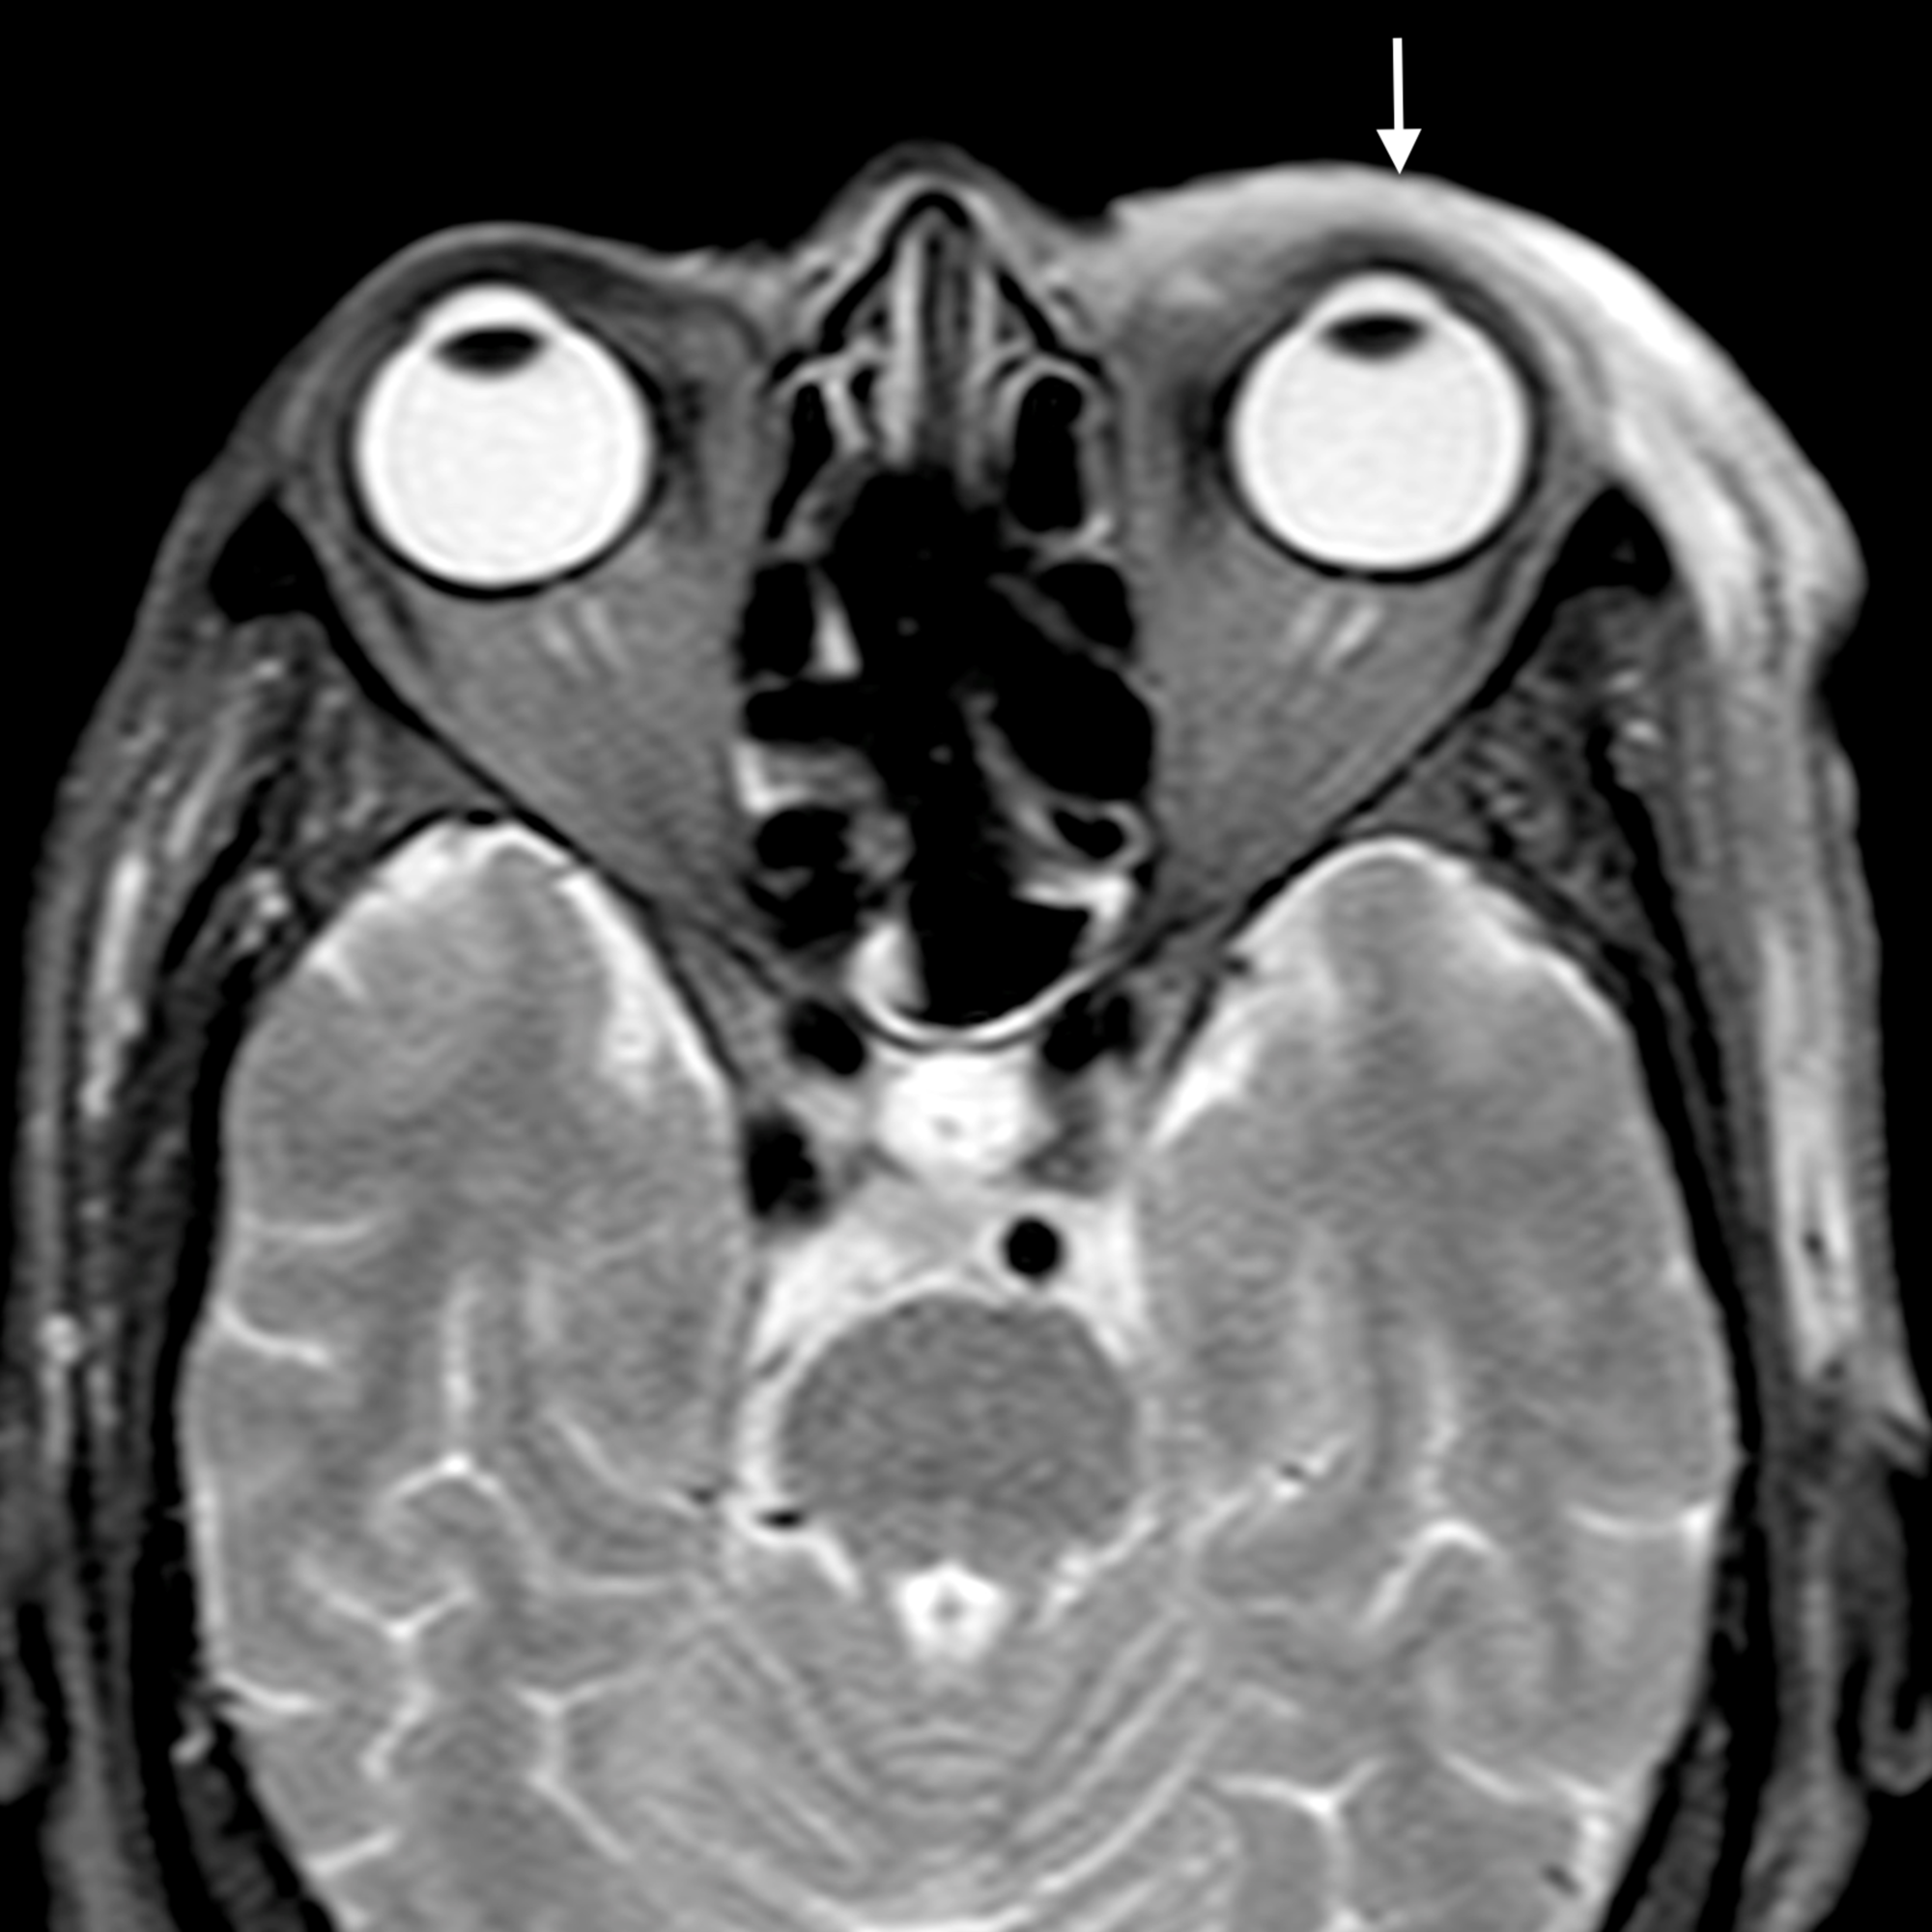

Orbital cellulitis causes diffuse, oedematous infiltration of the orbital connective tissue that is best demonstrated by the high signal intensity in T2-weighted fat-saturated sequences. Other findings are swelling and ill-defined margins of the extraocular muscles and exophthalmos [2]. Orbital cellulitis may be complicated by an abscess, which may form in the extraconal or intraconal orbit separate from the bone [3].

The main complications of orbital cellulitis (Figures 2-4) encountered in our study were:

1. An orbital abscess (Figures 5-6);

2. Preseptal cellulitis and abscess (Figures 7-8);

3. Periorbital cellulitis (Figures 9-10);

4. Dacryoadenitis (Figures 11-12);

5. Optic neuritis/perineuritis (Figure 13);

6. Cavernous sinus thrombophlebitis and thrombosis (Figure 14).

The most common complication of orbital cellulitis was orbital/periorbital abscess formation (eight cases, 53.3%), followed by optic neuritis (four cases, 26.67%), intracranial involvement (four cases, 26.67%), dacryoadenitis (three cases, 20%) and cavernous sinus thrombophlebitis (three cases, 20%).